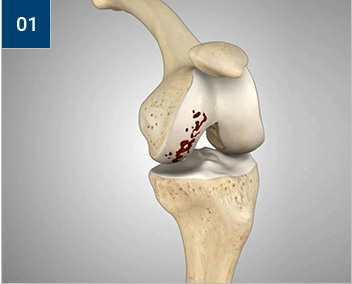

인공관절 부분치환술

손상된 경골과 대퇴골 관절면

슬관절 앞부분을 절개한 후 손상된 경골과

대퇴골 관절면 부위를 정교하게 다듬어줍니다.

경골과 대퇴골의 밑단부에 특수 금속을 씌웁니다.

금속 사이에 연골 역할을 해줄 특수플라스틱을

삽입합니다.

인공관절 부분치환술의 장점

인대 손상이 적습니다.

최소 절개로 시행되어 전 치환술에 비해 통증이

적고 재활이 빠릅니다.

골손실이 적어 합병증이나 감염의 위험이 적습니다.